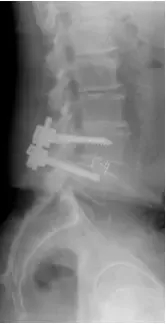

X-rays and MRI of the Lumbar spine showed L4-5 degenerative spondylolisthesis

and severe spinal stenosis.

Patient underwent decompression laminectomy with decompression of nerve roots and transforaminal interbody fusion using PEEK (polyether ether ketone) cage and pedicle screw and rod fixation for fusion at L4-5 level.

Fusion was achieved in about 3 months and patient was asymptomatic.